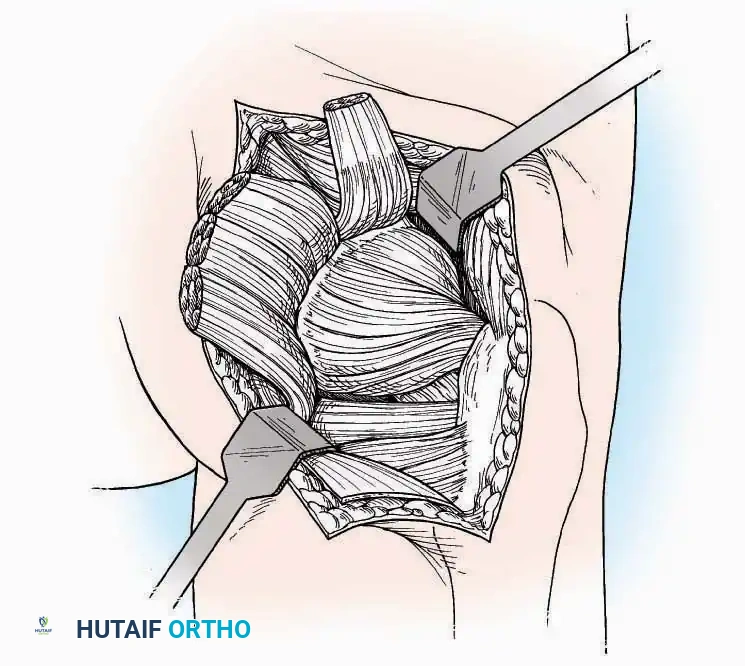

U Approach

Indications: Extensive plantar fasciotomy, radical tumor resection, or complex osteomyelitis debridement requiring access to the entire plantar surface of the calcaneus.

Positioning: Prone, with the leg supported on a large sandbag.

Surgical Technique:

* Incision: Join the medial and lateral approaches described above to form a large, continuous U-shaped incision around the posterior four-fifths of the calcaneus.

* Flap Elevation: Deepen the incision directly to bone. Elevate a massive plantar flap consisting of skin, the specialized fatty heel pad, and the plantar fascia. Retract this flap distally to expose the entire plantar calcaneal tuberosity.